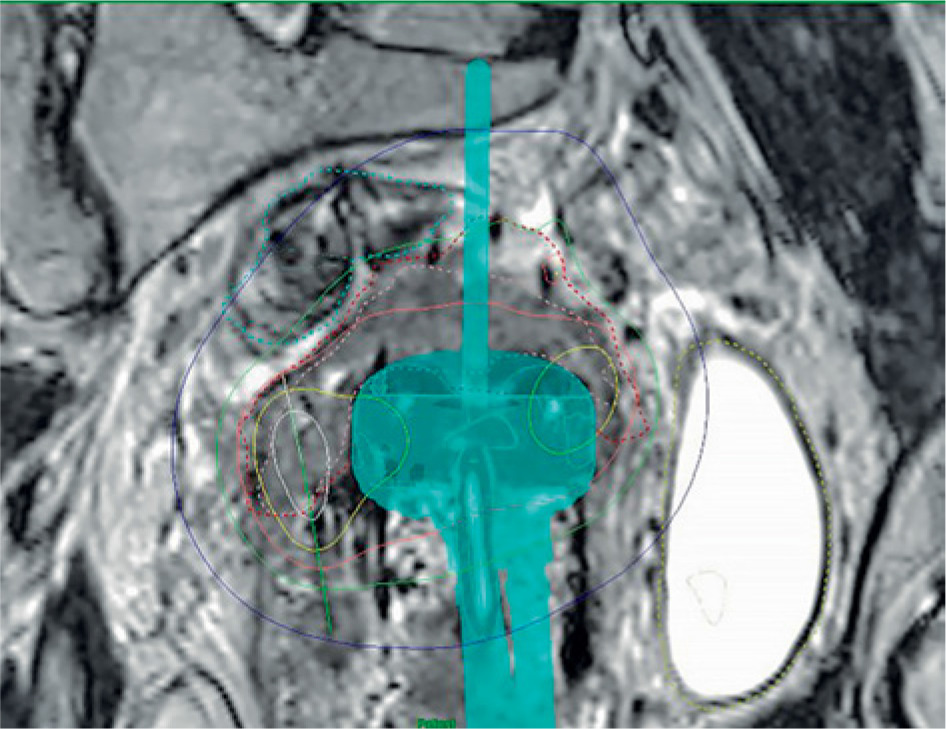

Indications for the use of FHNs include the whole uterine corpus that needs to be treated, intra-uterine tandem that is not reaching deep enough, when tumor at the parametrium of the cervix is out of reach of APNs, or tumor spread at vaginal wall. There are differences between various applicators; therefore, indications for the use of FHNs vary according to the applicator. Figure 1 demonstrate a case, where FHNs are needed for adequate dose coverage.

Fig. 1

Example of a plan with free-hand needles (FHNs) on the left (patient right) side of the applicator ring part. Oblique APN cannot reach the tumor. Green isodose = 7 Gy. Image is coronal view and rotated to visualize the needle